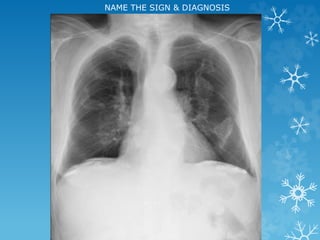

NAME THE SIGN & DIAGNOSIS

Corkscrew sign - midgut volvulus